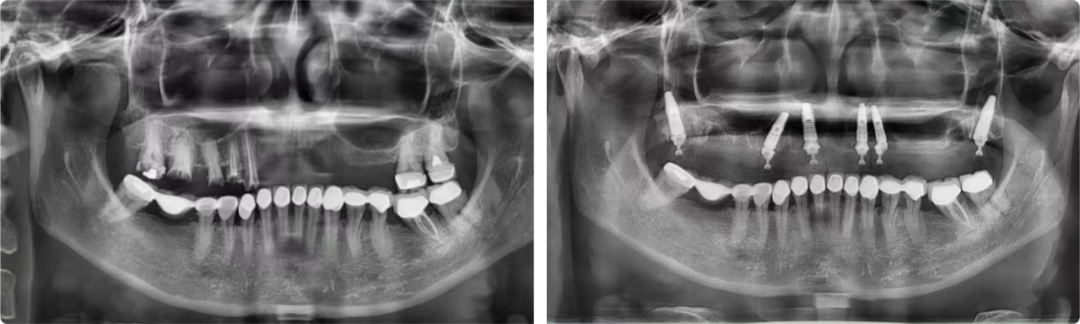

做完CBCT檢查,張潔發(fā)現(xiàn)患者的情況非常棘手:牙槽骨骨量不足、骨質(zhì)疏松,能選擇的種植點(diǎn)位非常有限且靠近上頜竇,種植體容易穿透,造成種植失敗。張潔為患者精心制訂了All-On-6半口即刻負(fù)重穿翼種植手術(shù)方案,這個方案難度很高,但效果最為理想。

患者術(shù)前術(shù)后全景片

這臺手術(shù)歷時三個半小時,比平時多花了一倍多時間,所幸的是六顆種植體全部成功負(fù)重。術(shù)后,患者順利戴冠,咬合良好。